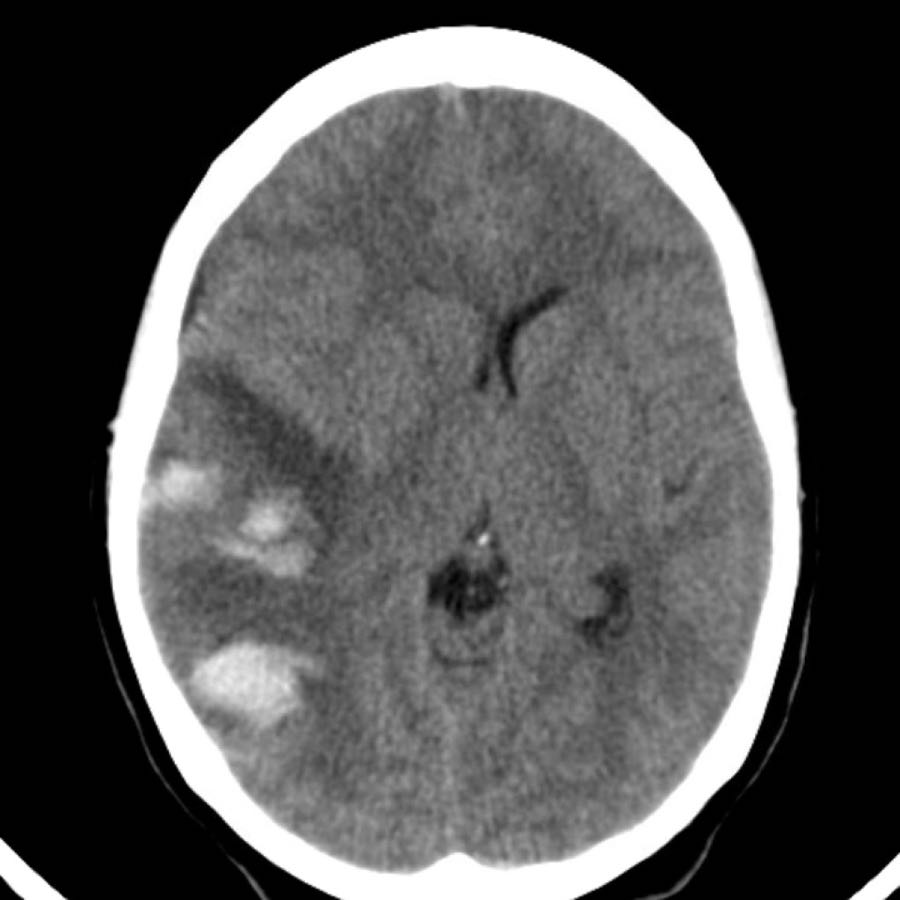

Các hình ảnh cho thấy xuất huyết tại hạch nền ở bệnh nhân tăng huyết áp lâu năm.

Tổn thương nằm tại đầu nhân đuôi.

Đầu nhân đuôi nhận máu từ động mạch Heubner và các động mạch thấu kính-vân.

Vỡ các động mạch này gây xuất huyết nhu mô não.

Sự hiện diện của tụ máu trong não thất được coi là yếu tố tiên lượng xấu do tắc nghẽn lưu thông dịch não tủy gây não úng thủy và tăng áp lực nội sọ.